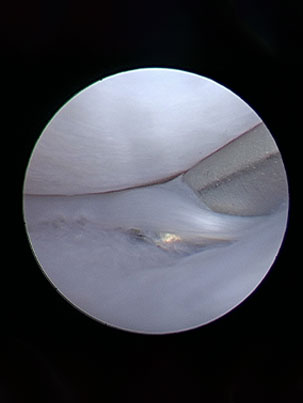

- Lameness/limping or a decrease in weight bearing of one or more limbs

- Abnormal angulation of a limb or a joint